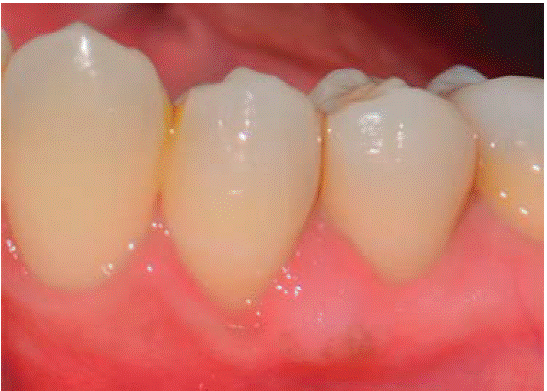

Al examen clínico se observa lesión gingival inflamatoria a nivel de piezas 3.4 y 3.5, de aproximadamente 15x9 mm, cubriendo la cara vestibular de la corona clínica, de consistencia firme, lobulada, textura rugosa y sangrante ante el estímulo (Figuras 1 y 2). A la evaluación periodontal no se detectaron bolsas periodontales, se observó presencia de placa, obteniéndose un índice de higiene oral (O'Leary) de 18.75%.